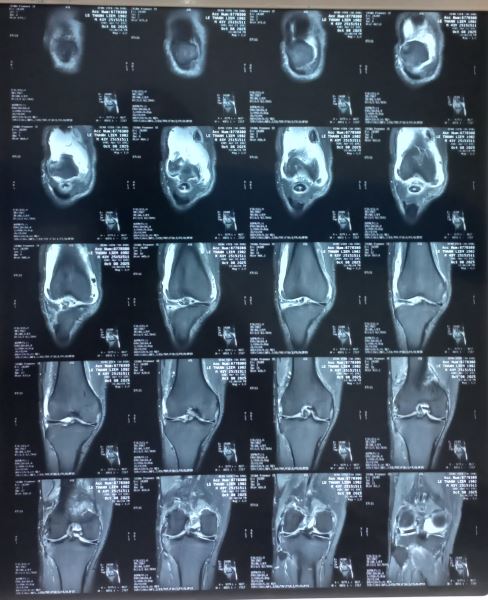

Chúng tôi nghĩ đến bệnh Synovial Osteochondromatosis một loại bệnh hiếm gặp và cho bệnh chân chụp MRI khớp cho kết quả sau: